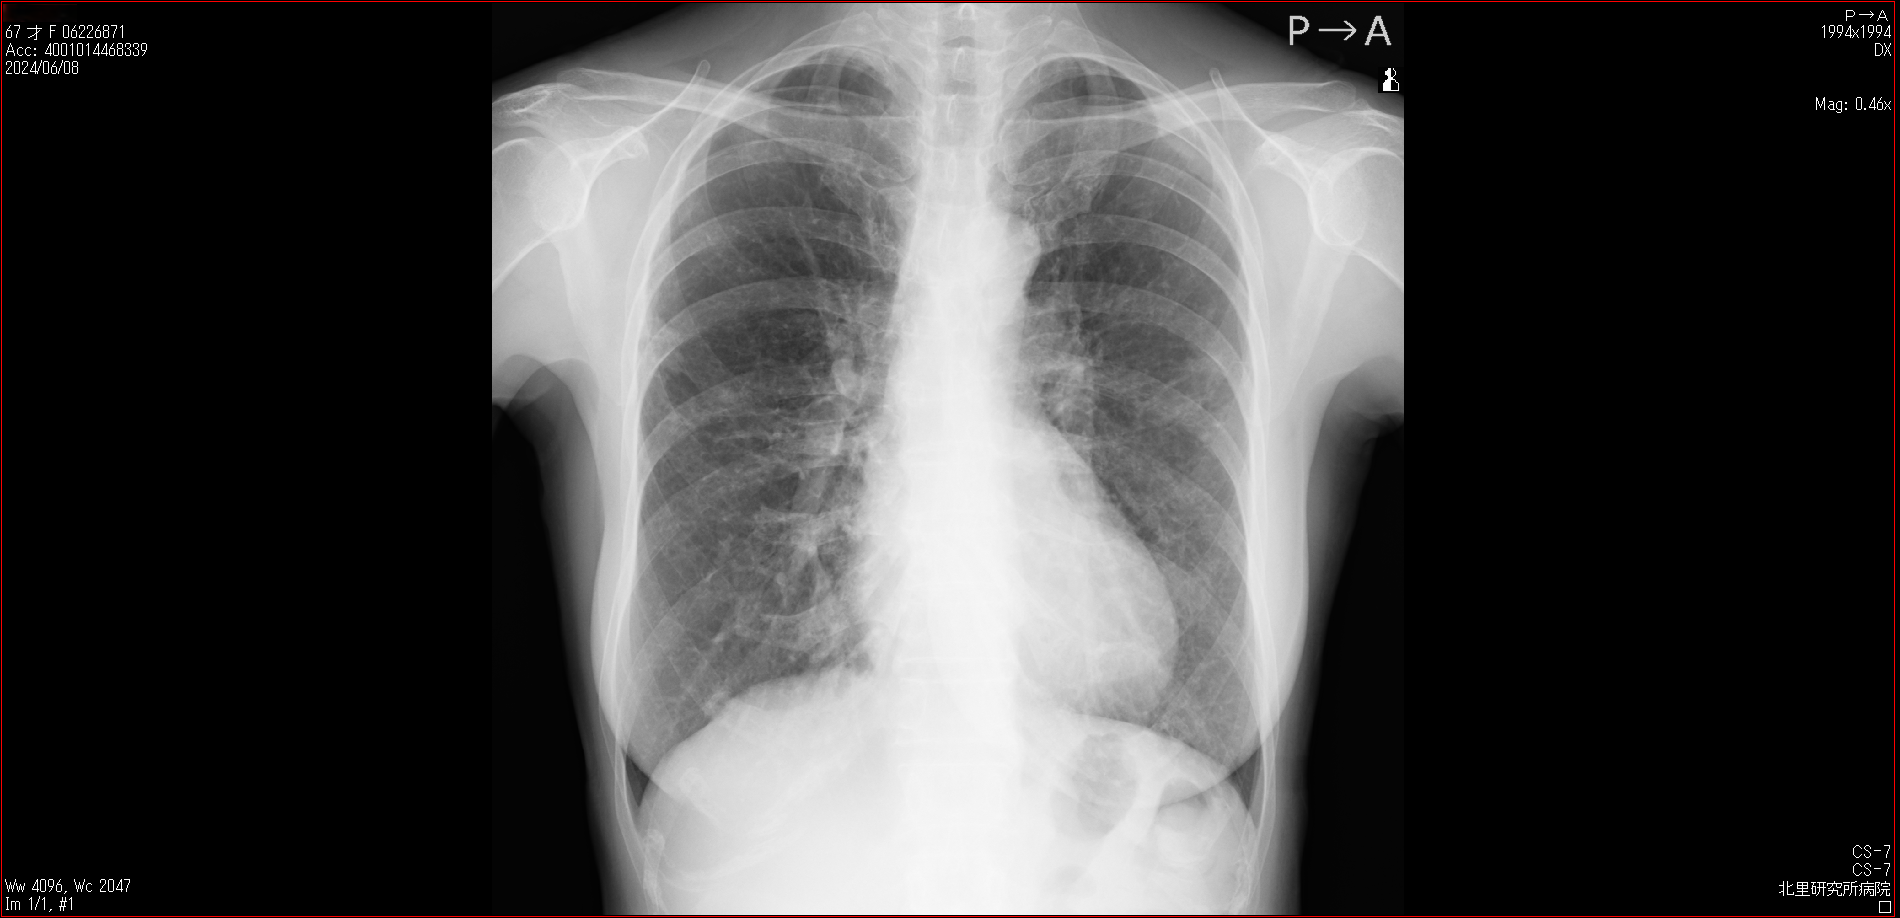

- 2024.06.08 転院後の要観察(1)(私立の病院Z)